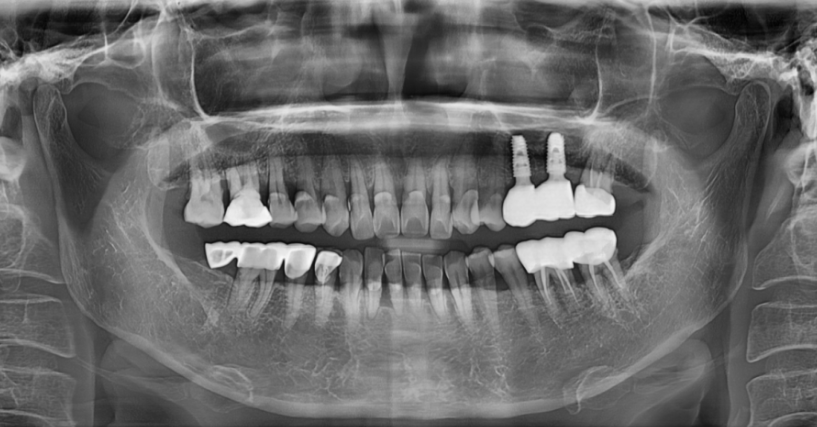

수술 후 보철이 올라갈 모습도 예측 가능합니다.

고령자나 만성 질환자 환자분에게도 부담이 적습니다.

계획된 대로 진행하기 때문에

시술 시간도 단축 됩니다.

불필요한 잇몸 절개도 없다보니

회복도 빠르고요.

이젠 감이 아닌 데이터로 하는 시대입니다.

예전처럼 잇몸을 열고,

잘 자리 잡길 바라며 심는 수술은 아닙니다.

서울 네비게이션 임플란트 치과에서

정확하게 심고, 빠르게 회복하세요.